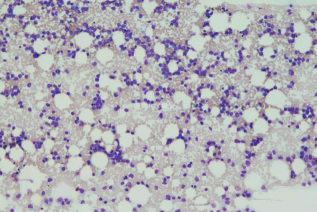

骨髓涂片:

可見大量異常細胞,比例及形態描述詳見后面的骨髓報告,一個突出的特點是原始細胞有核周淡染區。毫無疑問,該患者的白血病復發了。

▲POX染色:原始細胞為陽性,多為4+,偶為3+,團塊狀,多位于近核凹陷處

▲CE染色:部分原始細胞陽性

▲PAS:部分原始細胞為彌漫狀陽性,多位于近核凹陷處

▲NAE染色:原始細胞為陽性

▲NAE+NaF:原始細胞為陰性;重做一遍,還是一樣的結果

這樣的結果令筆者困惑:本例的原始細胞POX均為陽性,且陽性程度不低,CE也是陽性,均支持粒系;但本例的原始細胞NAE為陽性,且陽性可被NaF完全抑制,這又支持單系。到底是啥?

回顧一下該類疾病的細胞形態特點:核質發育顯著不平衡,胞質呈橘黃色或偏堿性,含中性顆粒,常有空泡;此處引用重慶大學附屬腫瘤醫院血液腫瘤實驗室楊再林教授的經典語錄:黃沙厚土出朝陽!出現局部的魚肚白/朝陽紅表示分化不好,而出現彌漫的黃沙樣則表示分化較好。

細胞化學染色:POX陽性至強陽性,呈團塊狀;氯乙酸AS-D萘酚酯酶(CE,粒細胞酯酶)也呈強陽性,α-NAE和α-NBE呈陰性或弱陽性,前者的陽性結果不被NaF抑制。而本例患者的細胞化學染色出現了NAE陽性且被NaF抑制的不典型表現。

不過,我們形態學工作者還是需要打破砂鍋問到底的精神,這樣才能不斷提高。雖然本例的原始細胞NAE為陽性,且可被NaF抑制,但其他特征均符合AML-M2b或AML伴t(8;21)(q22;q22.1);RUNX1-RUNX1T1,包括:有核周淡染區的原始細胞形態,POX的高陽性程度與酶型,CE的陽性,以及免疫分型檢測無單核系標記、CD19的表達等。